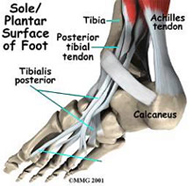

- Rotura del tendón de Aquiles

Sabemos que la rotura del tendón de Aquiles se produce con mayor frecuencia en varones entre los treinta y los cincuenta años y sabemos que es un mecanismo de contractura brusca lo que la desencadena pero no es muy bien conocida la causa que produce la debilidad del tendón. La rotura tiene lugar a 4 centímetros del anclaje calcáneo del tendón donde la nutrición del tendón es precaria por lo que se cree que existen factores tróficos implicados en la degeneración y rotura a este nivel. En cualquier caso, creemos oportuna la rápida sutura del tendón a través de una pequeñísima incisión aportando factores de crecimiento que estimulen y aceleren el proceso de cicatrización. - Fracturas del pie